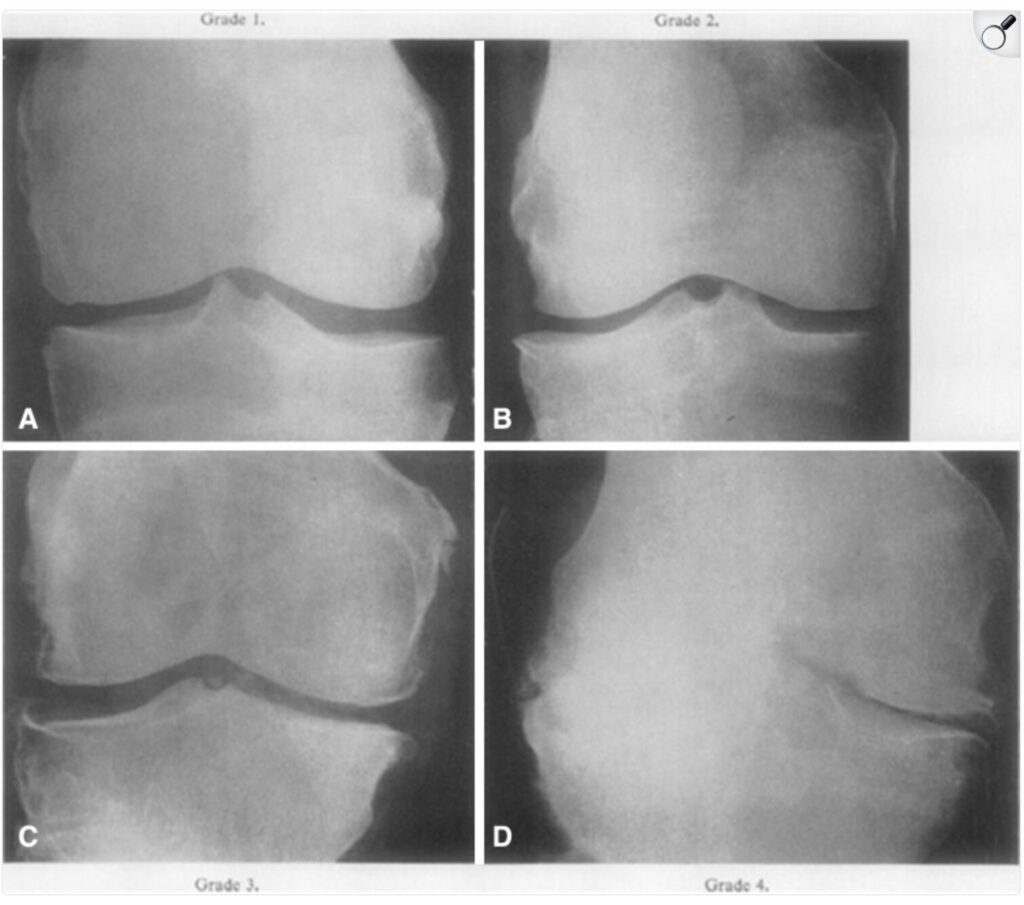

変形性膝関節症の重症度について

Kellgren-Lawrence 分類

グレード1 :大きな変化はないが、骨棘(骨のトゲ)の形成が疑われる状態

グレード2 :小さな骨棘形成があり、関節裂隙(関節の隙間)の狭小化の可能性がある。

グレード3 :骨棘が形成され、関節裂隙の狭小化が明確に確認できる。

グレード4 :顕著な骨棘形成と関節裂隙の著しい狭小化がみられる。